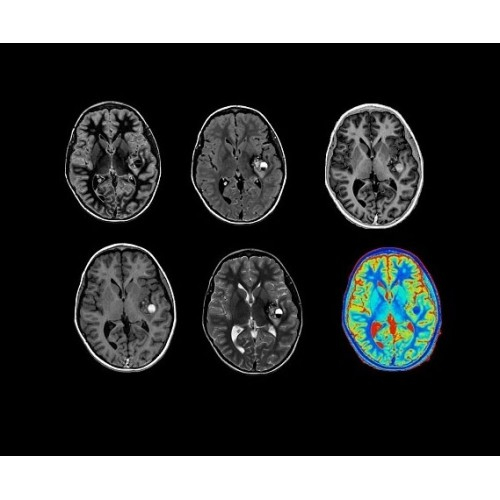

• NeuroWorks — универсальное решение для визуализации анатомии головного мозга, позвоночника, сосудов и периферических нервов с четкой дифференциацией тканей.

• 48-канальная катушка TDI для головы, входящая в базовую комплектацию SIGNA Architect, обеспечивает феноменальную производительность с учетом особенностей каждого пациента. Благодаря гибкому и универсальному дизайну, высокому соотношению сигнал/шум и передовым технологиям визуализации, таким как HyperWorks, учитываются потребности подавляющего большинства пациентов.